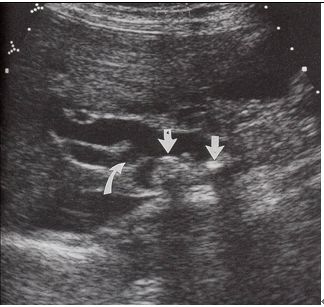

20. 55歲男性因為上腹痛合併發燒畏寒至急診,初步檢驗顯示WBC:13600 cells/mm3,seg:89%,Bilirubin(total):6.0 mg/dL,腹部超音波檢查如圖 所示,請問下列敘述何者為非? (A) 理學檢查摸不到脹大的膽囊,此為Courvoisier's law的基礎之一 (B) 患者血中AST/ALT可上昇,但絕不會超過5倍 (C) 血液培養常有葛蘭氏陰性菌 (D) 內視鏡治療為首選 (E) 治療成功後Bilirubin下降恢復的速度較Alkaline phosphatase來得快